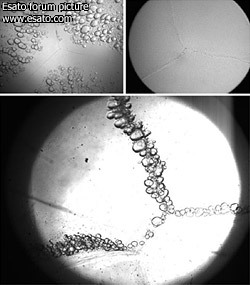

Microscope photographs of lenses incubated in organ culture conditions for 12 days. Right frame shows Control lens with no damage. Bottom frame demonstrates the effect of microwave radiation on bovine lens sutures for a total exposure of 192 cycles (1.1GHz, 2.22mW).Each cycle lasts 50min followed by 10 min pause. In the absence of microwave radiation, the bubbles are generated by temperature increase to 39.5 8C during 4 h; see left frame.